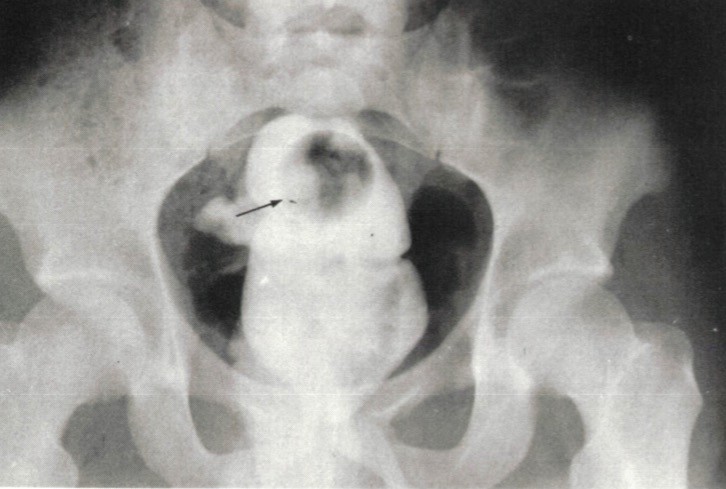

НемедицинаFigure 1. Рентгенограмма брюшной полости, показывающая уплотненную рентгеноконтрастную массу, заполняющую прямую кишку.

Обратите внимание на радиопрозрачный шарик для пинг-понга в верхней части (стрелка).